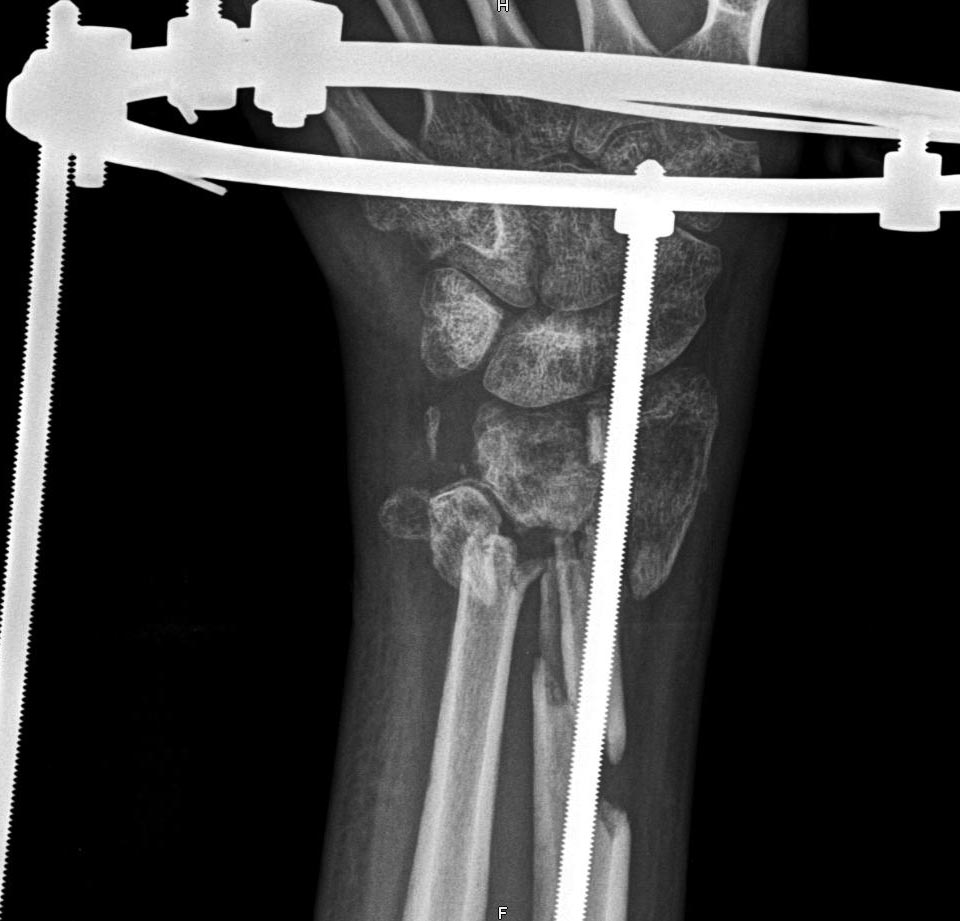

Многооскольчатый перелом костей предплечья.

Отрытый многооскольчатый перелом ДЕМ обеих костей предплечья со смещением.

АВФ - 8 недель. Пожалуйста, помогите определиться с дальнейшим оптимальным вариантом операции, пластики.

Дистракция избыточная.

На снимке - не ясна конструкция аппарата и что с его помощь можно сделать.